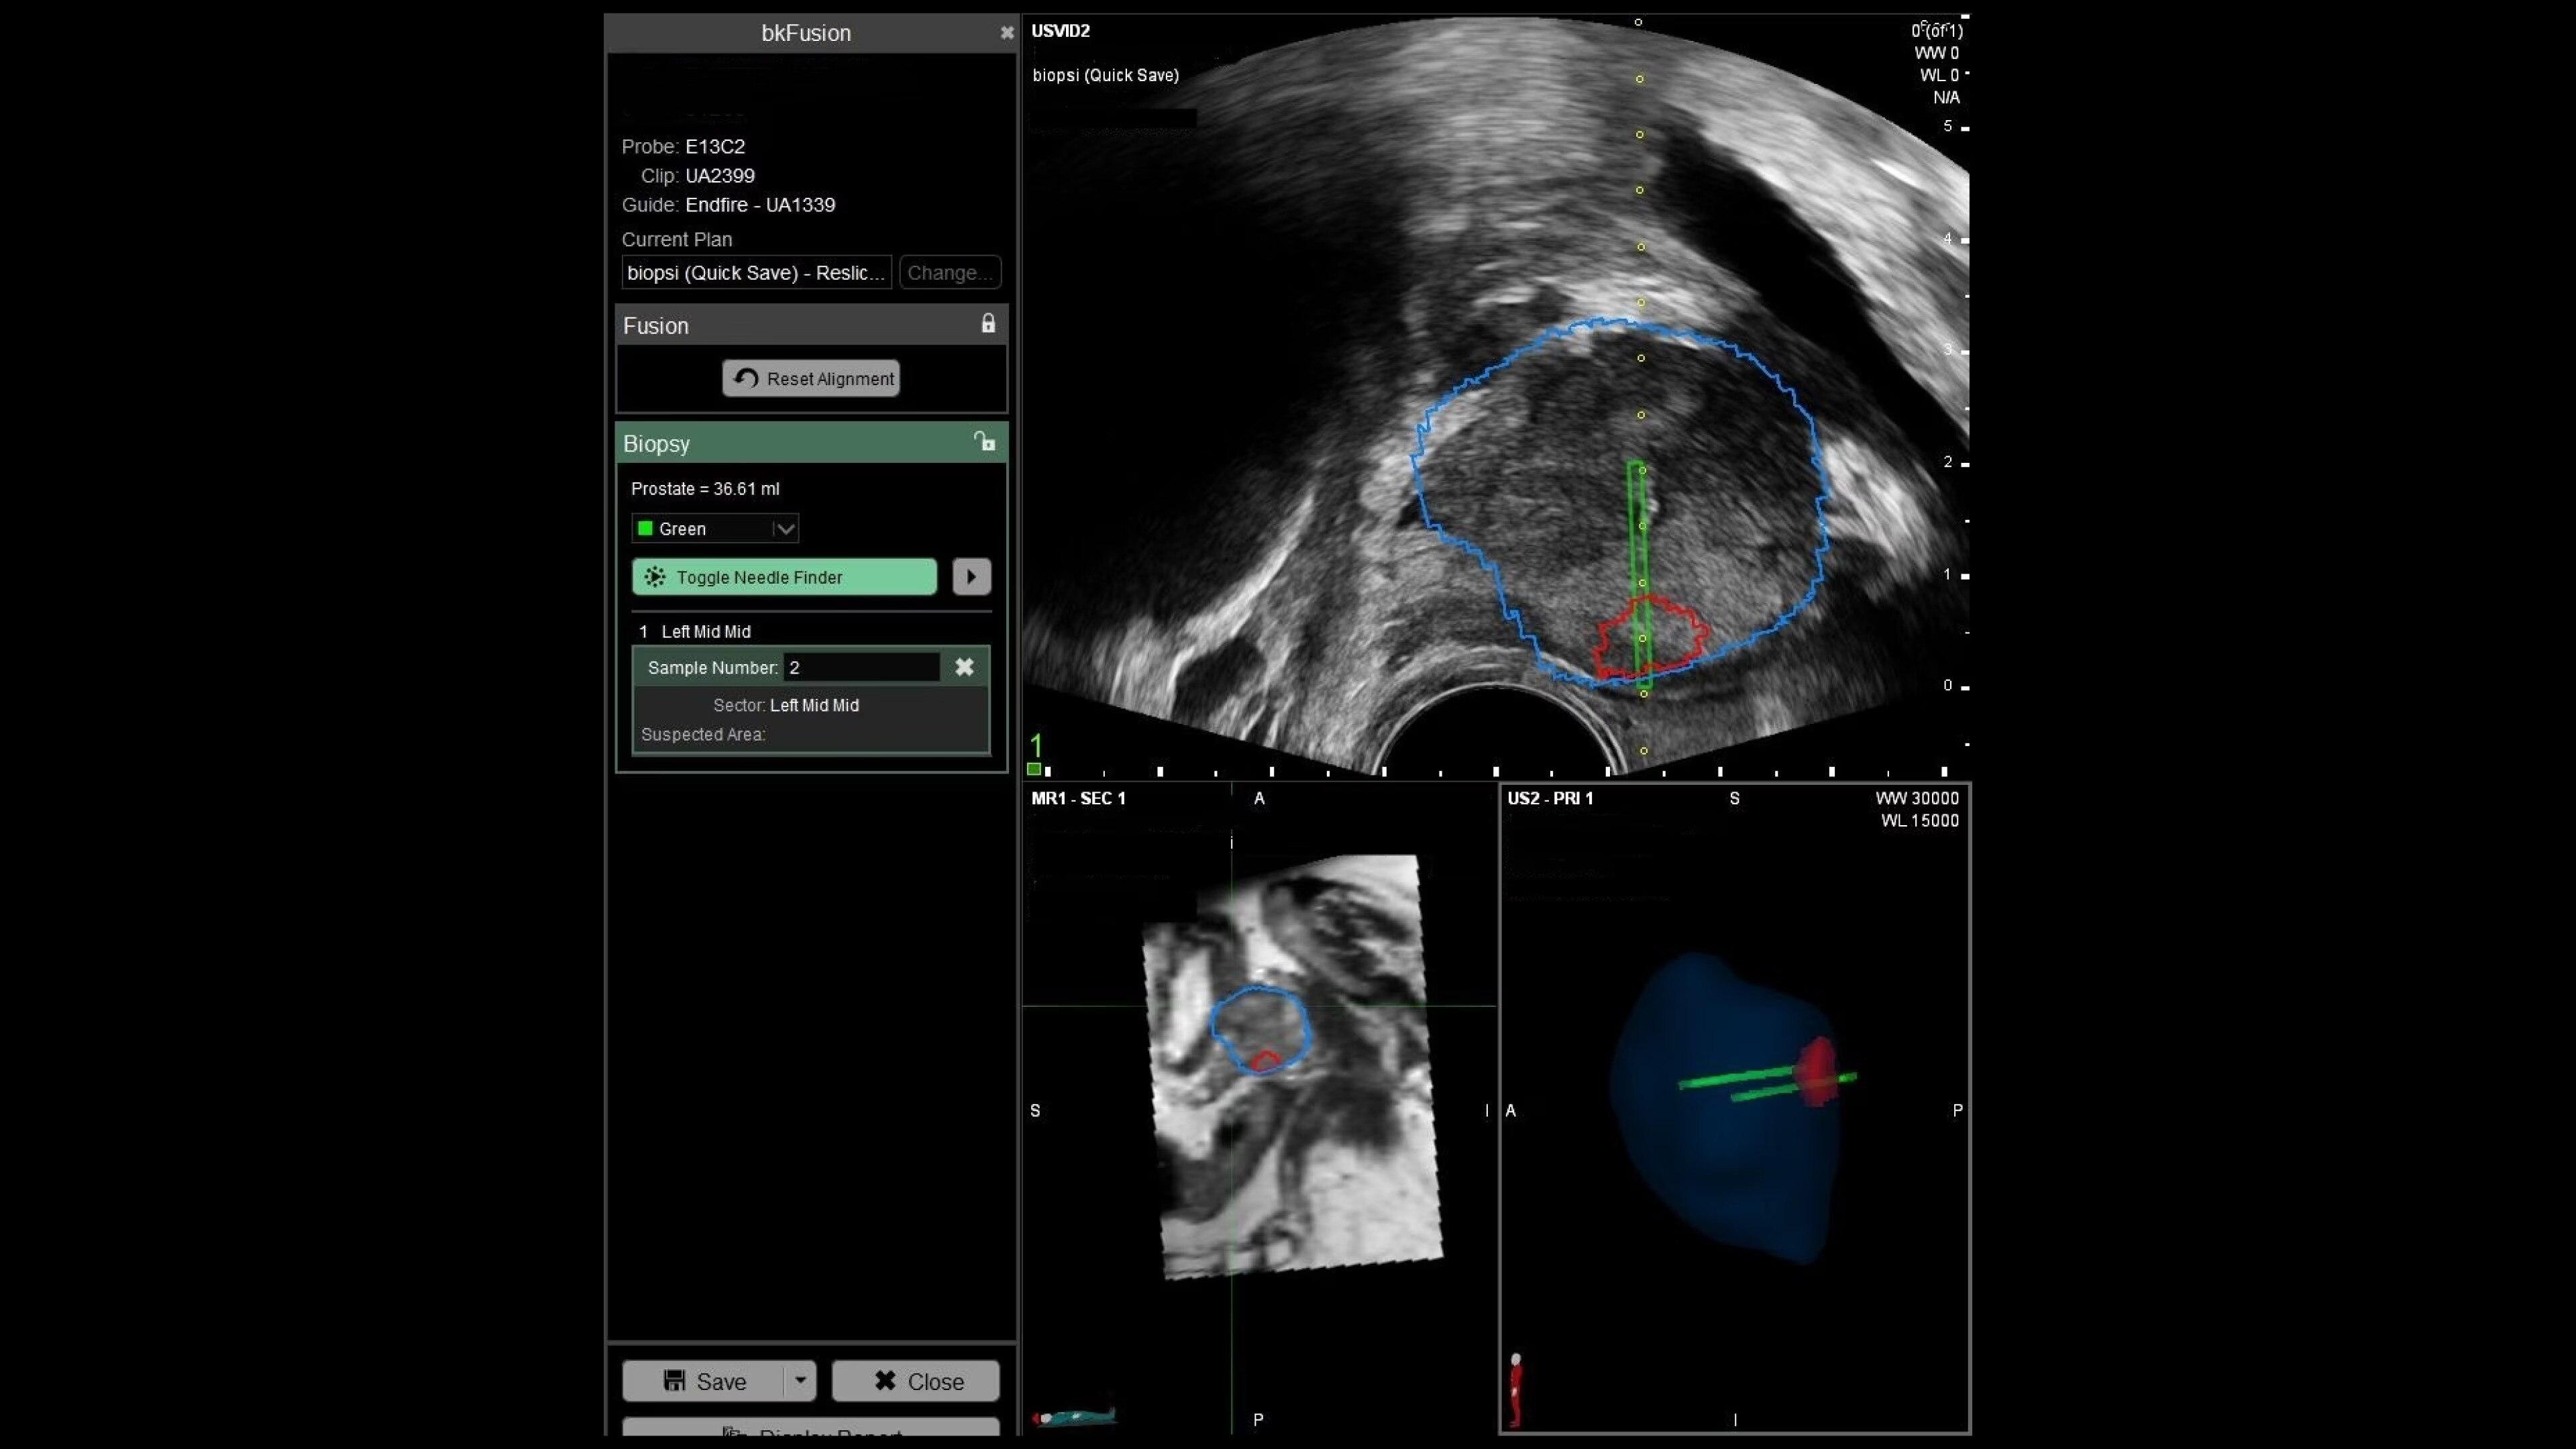

With bkFusion, confidently target your biopsy with clear visualization of organ borders to detect registration errors or deformations in real-time. bkFusion, MRI-ultrasound fusion biopsy solution features proprietary imaging algorithms developed with high spatial, temporal, and contrast resolution for advanced visualization.

bkFusion has proven to accurately detect 84% of PIRADS 3-5 lesions and up to 81% GG>=2 cancer.¹

Predictive Fusion®

Enhance biopsy accuracy with Predictive Fusion®

Predictive Fusion® is the proprietary registration method allowing you to imediately see any errors in the overly of MRI and ultrasound images before and during the procedure. Utilizing rigid 2D slice registration, it eliminates distortion in merging 3D shapes, ensuring precise MRI-ultrasound fusion. If changes are needed, make simple, one-touch, micro-adjustments to updte the registration without calibration steps or 3D sweeps. Enhance your prostate biopsy accuracy with this advanced technology.